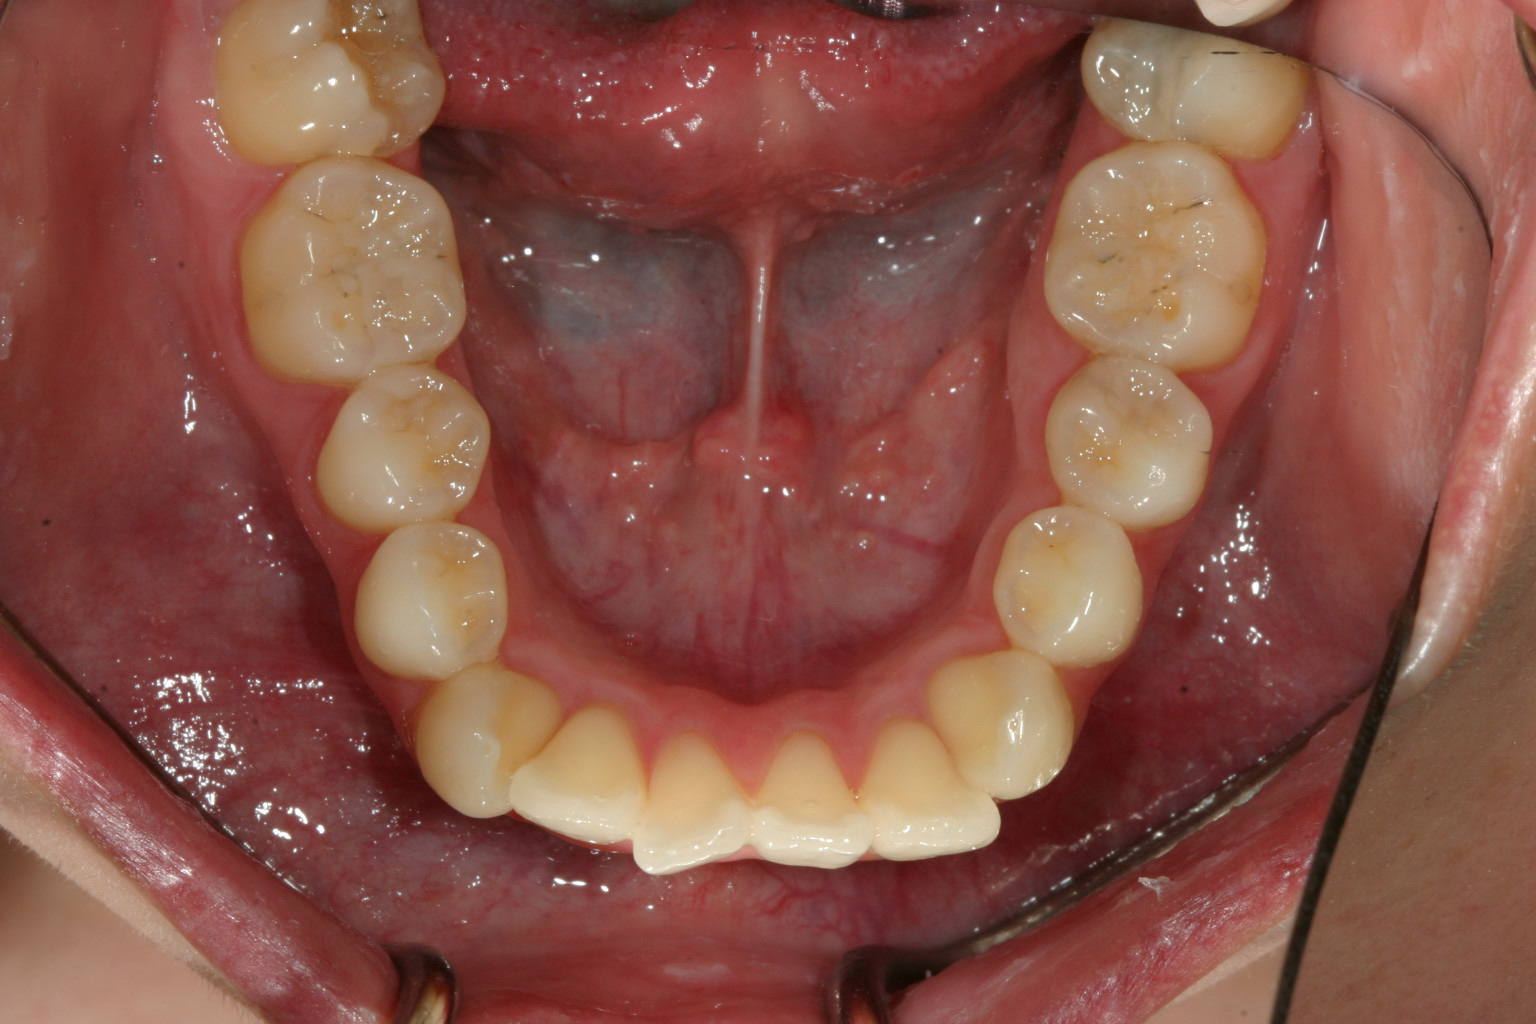

下顎に少し叢生が見受けられます。

下顎前歯も綺麗に並んでいます。